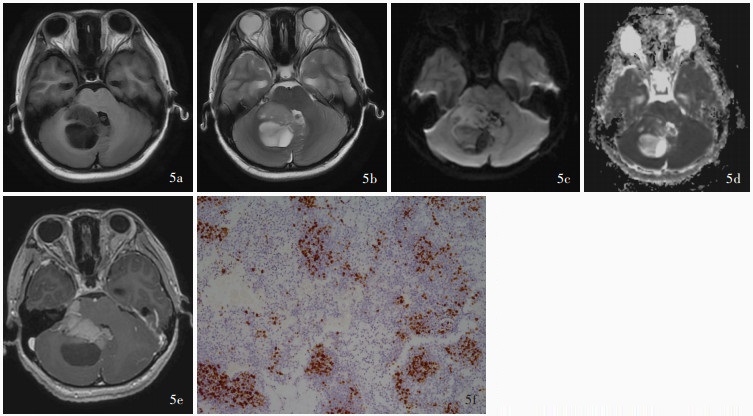

目的: 探讨儿童后颅窝常见肿瘤的影像学诊断与鉴别诊断方法,并按照先定位诊断再定性诊断的思路,基于DWI是否弥散受限提出儿童后颅窝常见肿瘤的诊断流程图。方法: 共纳入2021年1月至2024年1月在复旦大学附属华山医院予以手术切除的118例儿童后颅窝肿瘤患者,均行头部CT和MRI检查,并据此进行术前定位和定性诊断,分别以术中所见和术后病理学检查为诊断“金标准”,判断术前定位诊断和定性诊断的准确性;再基于DWI是否弥散受限提出儿童后颅窝常见肿瘤的诊断流程图。结果: 共118例后颅窝肿瘤患儿定位和定性诊断为第四脑室肿瘤计41例,包括髓母细胞瘤27例、毛细胞型星形细胞瘤7例、室管膜瘤5例、脉络丛乳头状瘤1例、形成菊形团的胶质神经元肿瘤1例;脑干肿瘤38例,包括弥漫性中线胶质瘤,H3 K27变异型24例、毛细胞型星形细胞瘤5例、海绵状血管瘤3例、儿童型弥漫性高级别胶质瘤(倾向弥漫性中线胶质瘤,H3野生型)2例、节细胞胶质瘤2例、非典型性畸胎样/横纹肌样肿瘤1例、儿童型弥漫性低级别胶质瘤1例;脑桥小脑角肿瘤计9例,包括毛细胞型星形细胞瘤3例、胆脂瘤2例、髓母细胞瘤1例、弥漫性中线胶质瘤,H3 K27变异型1例、毛细胞黏液型星形细胞瘤1例、尤文肉瘤1例;小脑肿瘤计30例,包括毛细胞型星形细胞瘤15例、髓母细胞瘤7例、海绵状血管瘤2例、室管膜瘤1例、儿童型弥漫性低级别胶质瘤1例、儿童型弥漫性高级别胶质瘤(倾向弥漫性中线胶质瘤,H3野生型)1例、胚胎发育不良性神经上皮肿瘤1例、错构瘤1例和肾外横纹肌样瘤小脑转移瘤1例。定位诊断,术前CT的定位诊断准确率为93.22%(110/118),MRI的定位诊断准确率达100%(118/118)。定性诊断,74例(62.71%)患儿定性诊断准确,23例(19.49%)诊断笼统,21例(17.80%)诊断错误。儿童后颅窝肿瘤的影像学鉴别诊断集中于髓母细胞瘤、毛细胞型星形细胞瘤、室管膜瘤、弥漫性中线胶质瘤,H3 K27变异型。位于脑干外的髓母细胞瘤、毛细胞型星形细胞瘤和室管膜瘤的DWI弥散受限发生率分别为100%(35/35)、4%(1/25)和5/6,3种肿瘤之间差异有统计学意义(Z=-5.601,P=0.000);位于脑干的弥漫性中线胶质瘤,H3 K27变异型和毛细胞型星形细胞瘤的DWI弥散受限发生率为79.17%(19/24)和1/5,两种肿瘤之间差异亦有统计学意义(Fisher确切概率法:P=0.038)。结论: 儿童后颅窝肿瘤早期诊断较为困难,DWI是鉴别诊断的重要依据,基于DWI是否弥散受限提出的儿童后颅窝常见肿瘤诊断流程图有望提高术前诊断的准确性。

Objective: To investigate the imaging diagnosis and differential diagnosis methods for common tumors in the posterior fossa of children, and to propose a flow chart for the diagnosis of common tumors in the posterior fossa of children based on the limited diffusion of DWI according to the idea of localization diagnosis followed by qualitative diagnosis. Methods: A total of 118 pediatric patients with posterior fossa tumors who underwent surgical resection in Huashan Hospital, Fudan University from January 2021 to January 2024 were enrolled, and all of them underwent head CT and MRI examinations, and preoperative localization diagnosis and qualitative diagnosis were carried out accordingly. Then, based on whether DWI was diffusion limited, a flow chart for the diagnosis of common tumors in the posterior fossa of children was proposed. Results: A total of 118 children with posterior fossa tumors were localization and qualitatively diagnosed, including 41 cases of fourth ventricular tumors, including medulloblastoma (27 cases), pilocytic astrocytoma (7 cases), ependymoma (5 cases), choroid plexus papilloma (one case), and rosette-forming glioneuronal tumor (RGNT, one case). There were 38 cases of brainstem tumors, including 24 cases of diffuse midline glioma, H3 K27-altered, 5 cases of pilocytic astrocytoma, 3 cases of cavernous hemangioma, 2 cases of pediatric-type diffuse high-grade glioma (prone to diffuse midline glioma, H3 wild type), 2 cases of ganglio glioma, one case of atypical teratoid/rhabdoid tumor (AT/RT), and one case of pediatric-type diffuse low-grade glioma. There were 9 cases of cerebellopontine angle (CPA) tumors, including 3 cases of pilocytic astrocytoma, 2 cases of cholesteatoma, one case of medulloblastoma, one case of diffuse midline glioma, H3 K27-altered, one case of pilomyxoid astrocytoma, and one case of Ewing sarcoma. There were 30 cases of cerebellar tumors, including 15 cases of pilocytic astrocytoma, 7 cases of medulloblastoma, 2 cases of cavernous hemangioma, one case of ependymoma, one case of pediatric-type diffuse low- grade glioma, one case of pediatric-type diffuse high- grade glioma (prone to diffuse midline glioma, H3 wild type), one case of dysembryoplastic neuroepithelial tumor (DNT), one case of hamartoma, and one case of extrarenal rhabdomyomatoid tumor cerebellar metastases. Localization diagnosis, the accuracy of preoperative CT was 93.22% (110/118), while the accuracy of preoperative MRI was 100% (118/118). Qualitative diagnosis, 74 cases (62.71%) had accurate qualitative diagnosis, 23 cases (19.49%) had general diagnosis, and 21 cases (17.80%) had wrong diagnosis. The imaging differential diagnosis of posterior fossa tumors in children focuses on medulloblastoma, pilocytic astrocytoma, ependymoma, and diffuse midline glioma, H3 K27-altered. The incidence of limited diffusion of DWI in medulloblastoma, pilocytic astrocytoma and ependymoma outside the brainstem was 100% (35/35), 4% (1/25) and 5/6, and the difference among the three tumors was statistically significant (Z =-5.601, P = 0.000). The incidence of limited diffusion of DWI in diffuse midline glioma, H3 K27-altered and pilocytic astrocytoma in the brainstem was 79.17% (19/24) and 1/5, and the difference between the two tumors was also statistically significant (Fisher's exact possibility: P = 0.038). Conclusions: The early diagnosis of posterior fossa tumors in children is difficult, and DWI is an important basis for differential diagnosis.